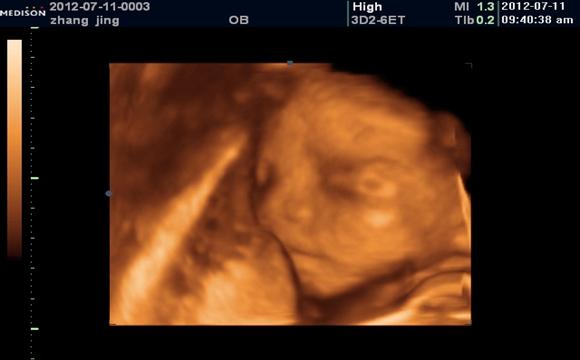

很多孕妈知道自己怀孕之后,就会特别好奇到底是男孩女孩呢?每天都在盼望着,就等着做四维彩超的时候让医生给看一下男孩女孩。

目前如果想要知道男孩女孩,只能借助医学手段,但是现在临床上是不允许进行胎儿性别鉴定的,毕竟担心会有选择性别的出现,这样就得不偿失了,总之,大家好奇归好奇,尽量不要直接问医生,以免医生不高兴影响检查哦。